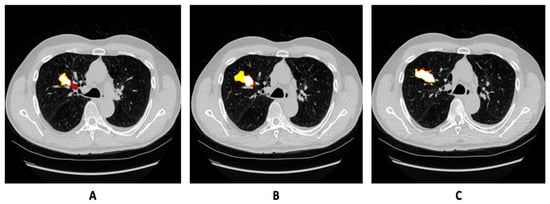

3.1. Dataset